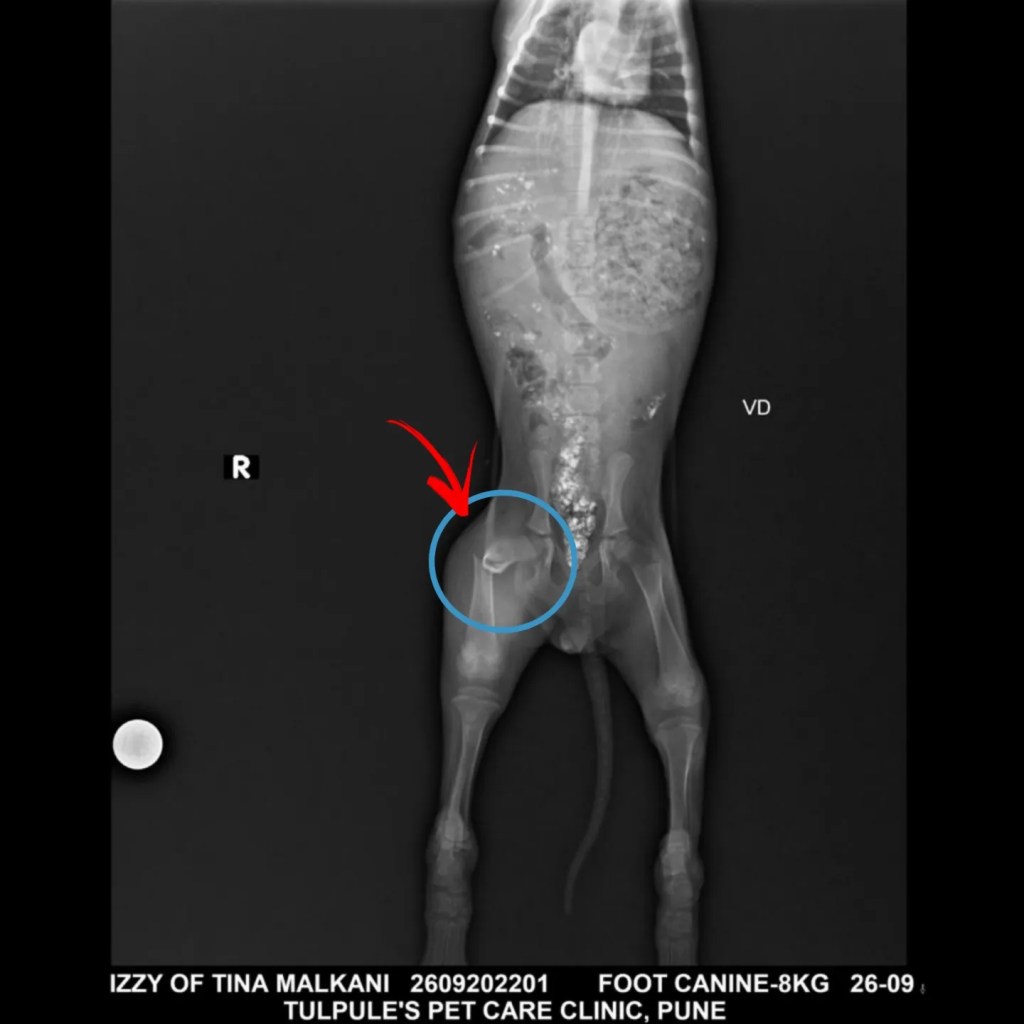

Looks like Izzy was hit by a vehicle or no idea what but just see that break 💔 SWIPE to see the xray…

It’s at such a spot where we can’t even put a plaster .. so she’s on calcium supplements and painkillers along with cage rest.

She will take at least 4 weeks to recover and heal. We are not going in for the surgery option because she is just too tiny..

Since she is so young, her bones will fuse and she will walk pain free again. She won’t have a perfect walk but she will not be in pain for sure.